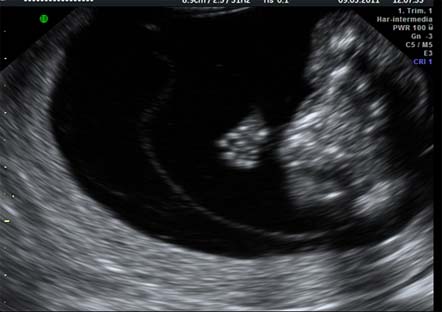

En los riesgos intermedios, entre 1/270 y 1/1000, hay disparidad de criterios en cuanto a lo que hacer en estos casos debido a que los pocos falsos negativos del cribado ocurren en este intervalo. Algunos ginecólogos abogan por la realización de una ecografía entre las semanas 11 y 14 para localizar algún marcador sugerente de que el feto sea portador de una alteración cromosómica. Entre ellas –quizá os suene– está el hueso nasal , ductus venoso, regurgitación tricuspídea y ángulo fronto-maxilar.